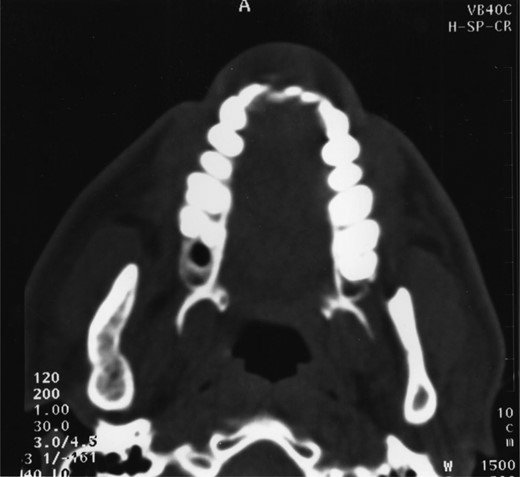

Radiographic examination over the following few months showed new bone formation and within 9 months of the initial biopsy the drain was expelled by formation of new bone (Fig. 3). One year after the commencement of treatment the patient was admitted for enucleation of the cystic remnant. At the time of this procedure a small cyst was removed from the right upper ramus and condylar neck, together, with a separate cyst associated with the lower right wisdom tooth. The patient made an uneventful post-operative recovery and histology revealed two KCOTs with a thick parakeratinized type of epithelium typical of radicular cysts.

Demonstrates bony infill with the nasopharyngeal tube in place.